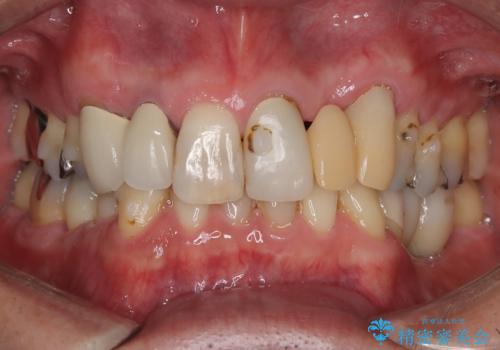

- 主訴:すっと仮歯の前歯を綺麗にしたい

左上1番目~3番目にかけてブリッジの仮歯が入った状態で来院された患者さんで、左上3に縁下カリエスを認め抜歯してインプラントか牽引(エクストリュージョン)を行うか、歯肉根尖側移動術を行うか選択いただき牽引の後補綴処置を行うこととしました。